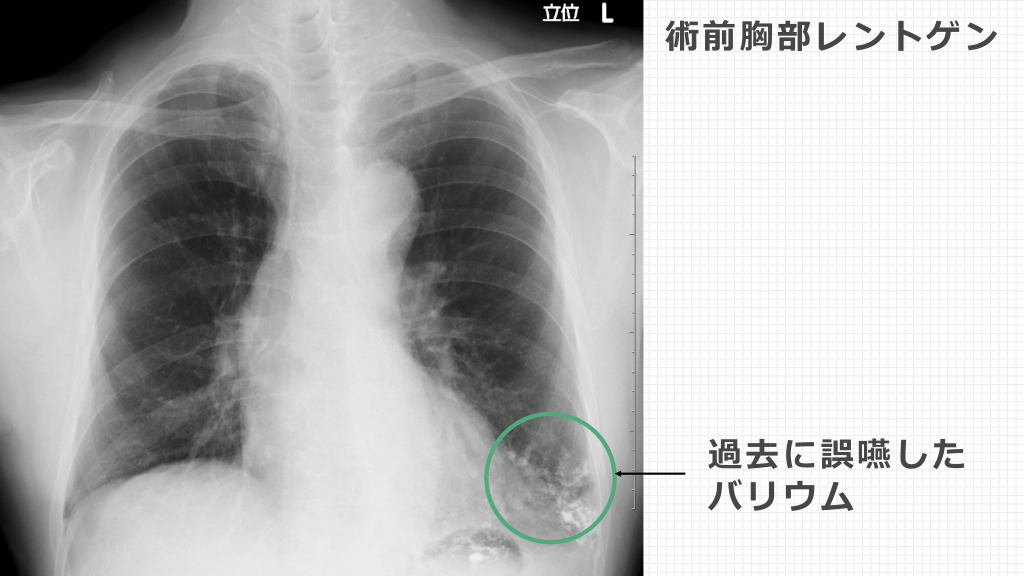

Case02 基礎情報 ・75歳 男性 • 既 往 歴 : 56歳時、バリウムによる誤嚥性肺炎 現病歴 2015年1⽉より喀⾎があり、九州の5施設を受診した 末に、喀⾎・肺循環センターにご紹介となった。

術前胸部レントゲン 過去に誤嚥した バリウム

CTangio バリウム貯留部は気管⽀拡張症になっている。